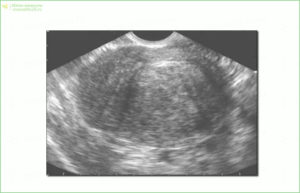

Эндовагинальная и брюшная сонограмма (УЗИ)

Интравагинальное и брюшное ультразвуковое исследование помогут подтвердить наличие, определить расположение аденомиоза или миомы, а также покажут состояние яичников.